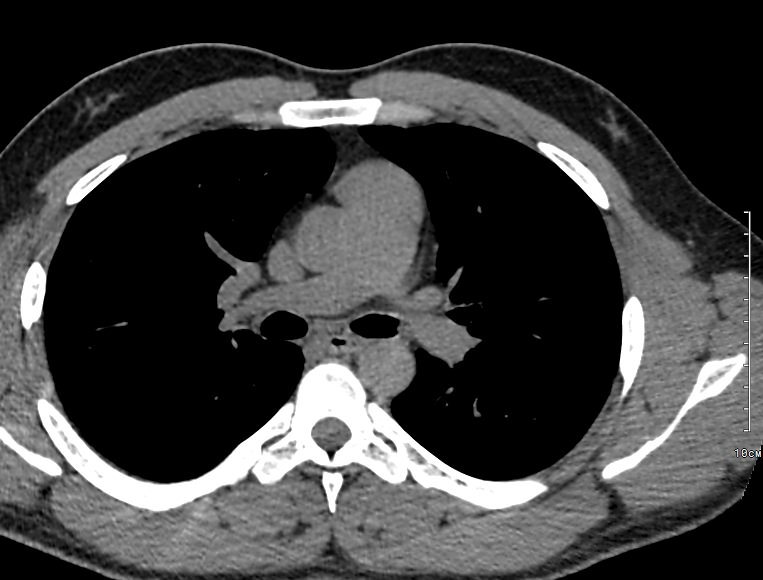

Наиболее информативным современным способом визуализации лимфоузлов является мультиспиральная компьютерная томография. Методика предусматривает послойное сканирование исследуемой области при помощи проникающего действия рентгеновских лучей.

В нашей клинике КТ лимфатических узлов средостения проводится на новейших мультиспиральных томографах экспертного уровня, которые производят тончайшие срезы исследуемой зоны толщиной от 0,5 мм и позволяют визуализировать лимфоузлы и прилегающие мягкие ткани с высокой детализацией. Увеличенное количество высокочувствительных детекторов аппарата обеспечивает высокую разрешающую способность и четкость изображений, при этом позволяет выполнить исследование в течение нескольких секунд с минимальной дозой облучения.

Методика КТ позволяет оценить структуру лимфатических узлов, обнаружить неоднородность, гиперплазию, деформацию их контуров.

Информация, полученная при помощи мультиспиральной компьютерной томографии, дает возможность визуализировать размеры лимфоузлов, их точную локализацию, взаимодействие с близлежащими органами и окружающими тканями, образование пакетов и конгломератов лимфоузлов, выявить инфильтрацию прилегающих анатомических областей.